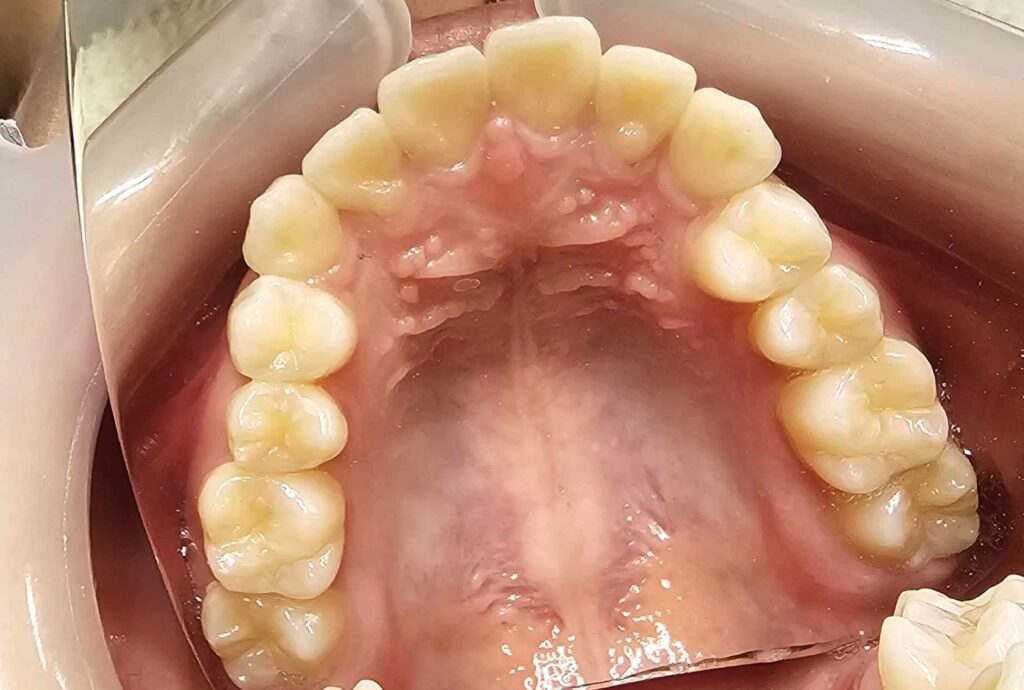

治療前

- 初診:2016年、9歳女児

- 主訴:出っ歯と歯の隙間がきになる。

- 診断:2級過蓋咬合、上下永久歯(犬歯)萌出スペース不足

- 治療方針:非抜歯で行う。虫歯予防(フッ素)、歯磨き指導、上下拡大床→咬合関係改善のツインブロック(2級→1級関係へ)→マウスピース矯正→下親知らずの抜歯、保定→メンテナンス